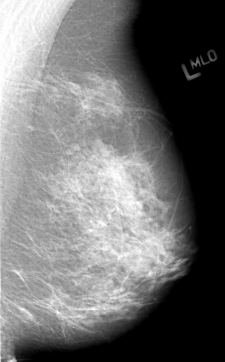

B_3012_1.LEFT_MLO

LEFT_MLO LINES 4336 PIXELS_PER_LINE 2696 BITS_PER_PIXEL 12 RESOLUTION 50 NON_OVERLAY